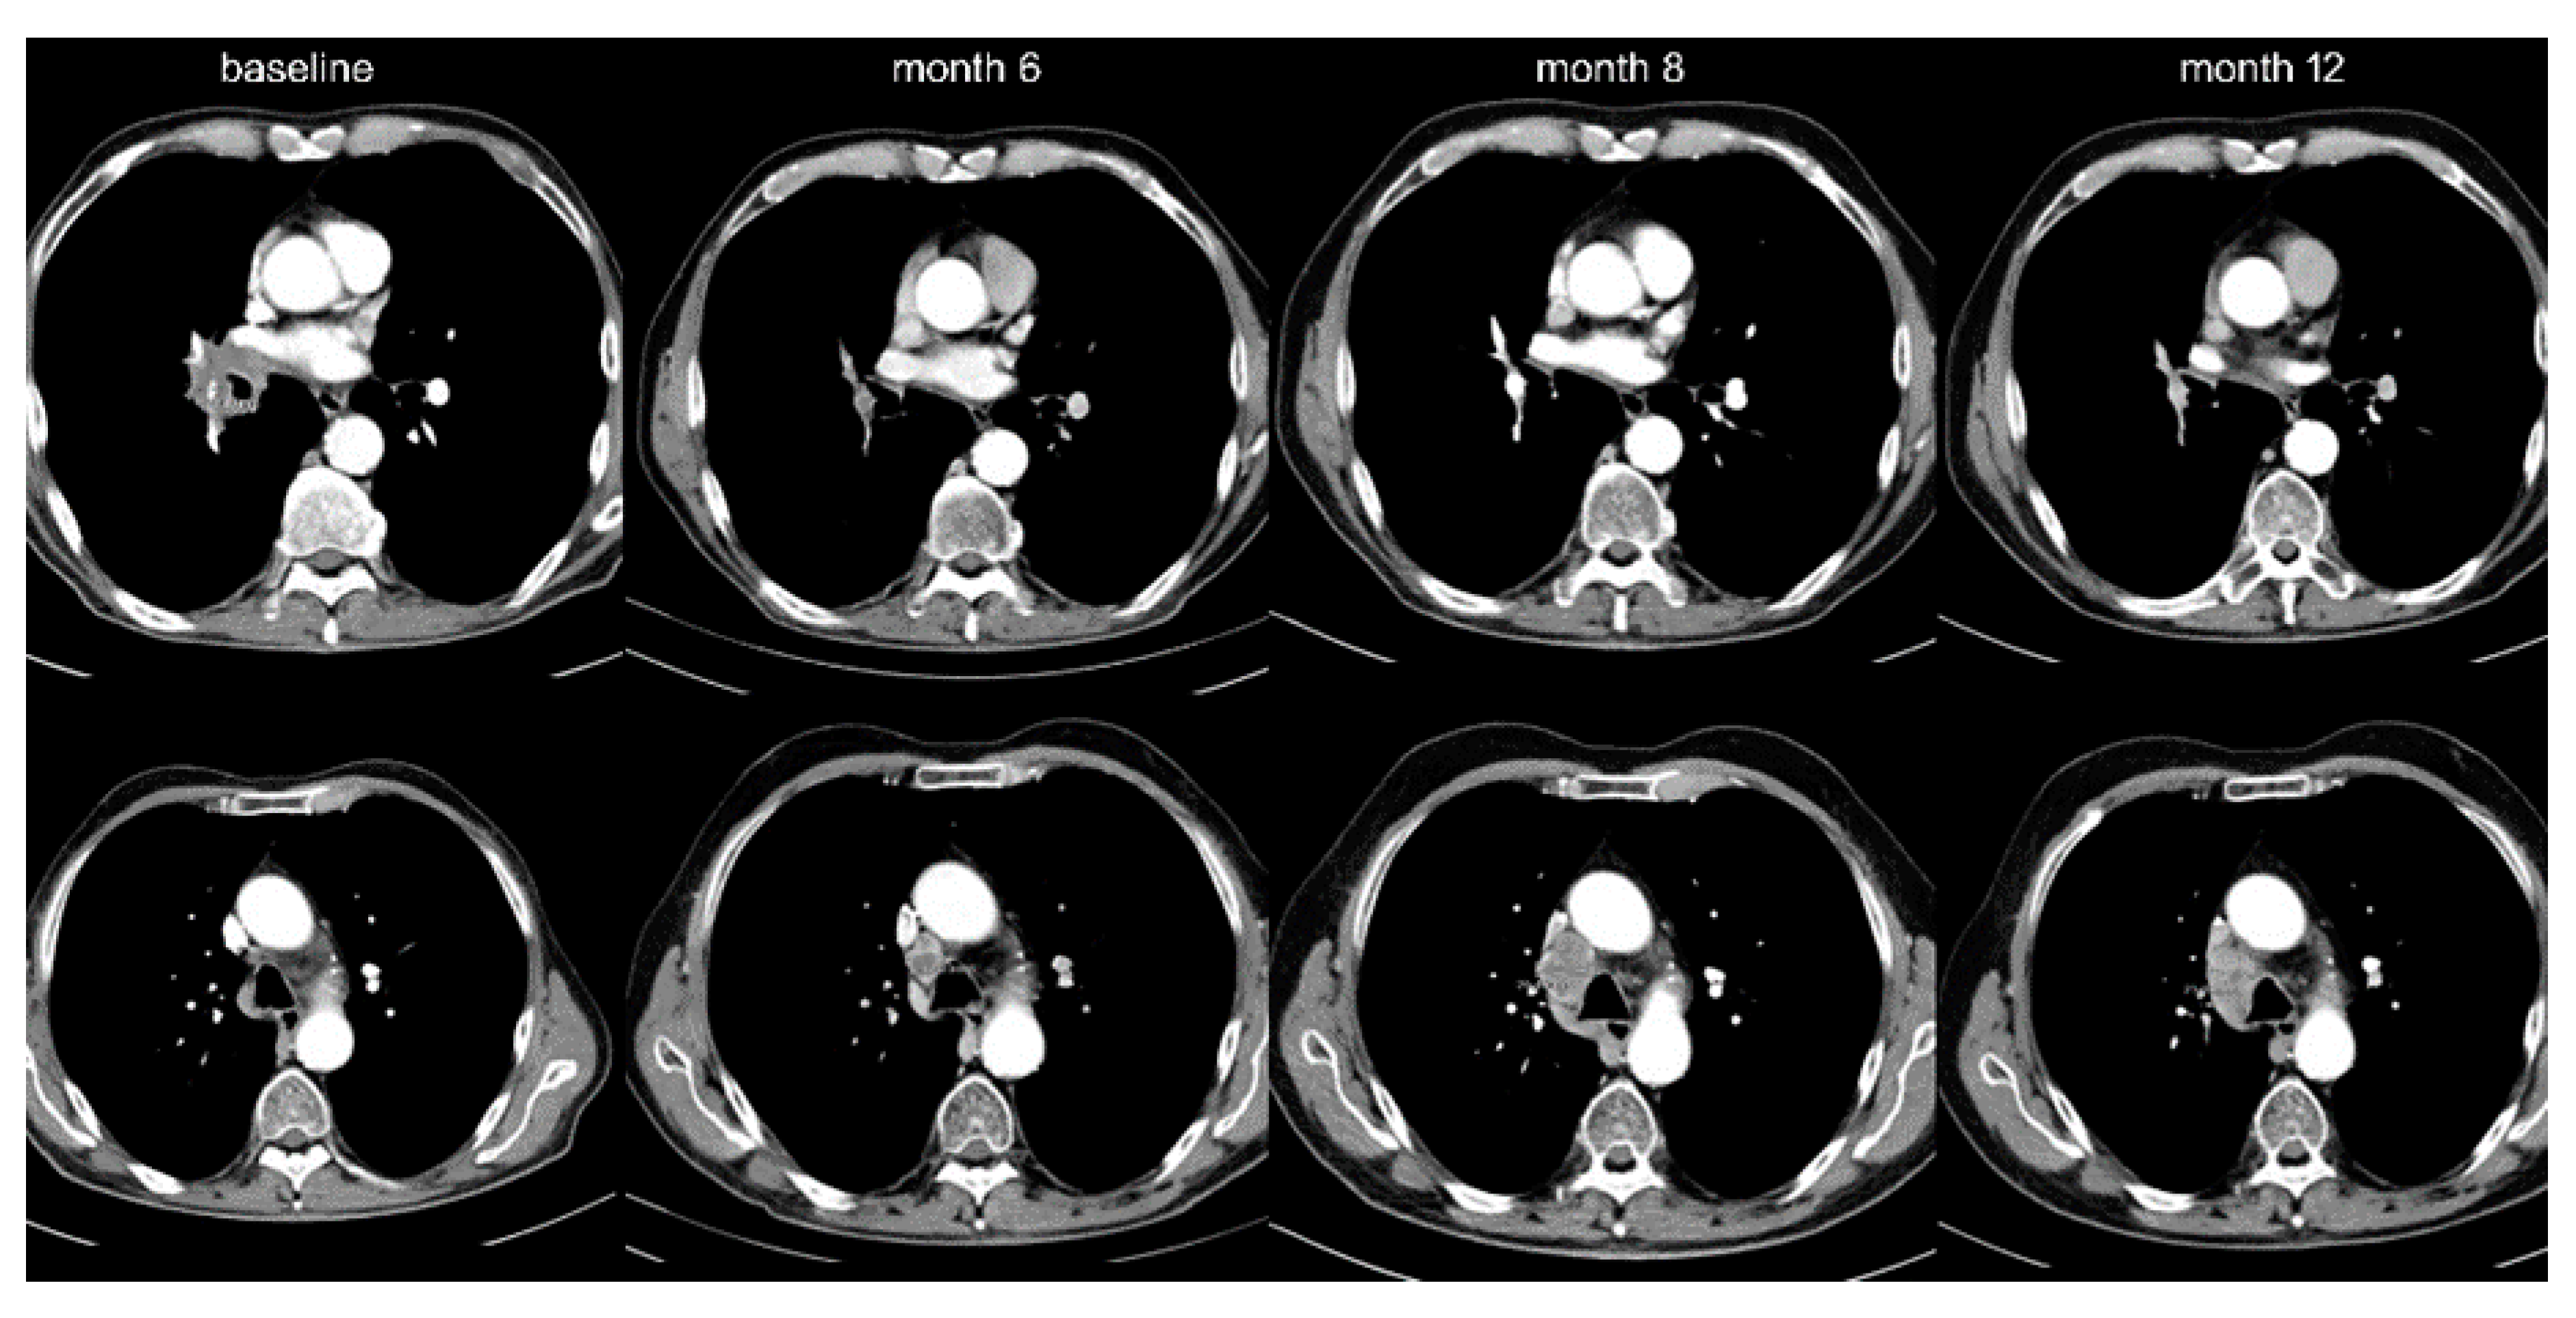

- Tetzlaff, M.T.; Nelson, K.; Diab, A.; Staerkel, G.A.; Nagarajan, P.; Torres-Cabala, C.A.; Chasen, B.A.; Wargo, J.A.; Prieto, V.G.; Amaria, R.N.; et al. Granulomatous/sarcoid-like lesions associated with checkpoint inhibitors: A marker of therapy response in a subset of melanoma patients. J. Immunother. Cancer 2018, 6, 14. [Google Scholar] [CrossRef] [PubMed]

- Gkiozos, I.; Kopitopoulou, A.; Kalkanis, A.; Vamvakaris, I.N.; Judson, M.A.; Syrigos, K.N.; Ioannis, V.N.; Syrigos, K.N. Sarcoidosis-Like Reactions Induced by Checkpoint Inhibitors. J. Thorac. Oncol. 2018, 13, 1076–1082. [Google Scholar] [CrossRef]